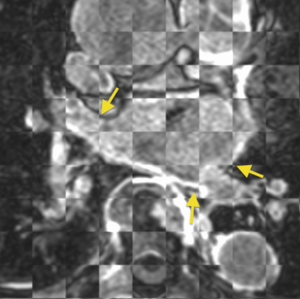

Automatically selected correspondences

• We need a more accurate registration pipeline for the pulmonary veins.

• To explore ideas for establishing correspondence (via registration or other means) between points on the surface of the pulmonary veins (PV) and PV antrum near the left atrium in pre-RF-ablation DEMRI images with post-RF-ablation DEMRI images to within about 2 mm precision. This may be an impossible task (or impossible to validate the results, anyway), but there are many important application areas for AF research and clinical treatment if we can do it. For the Project Week, our main goal is to explore possibilities with available NAMIC expertise and Slicer tools during the meeting. If a likely algorithm can be identified, we will plan a Slicer module to implement it.